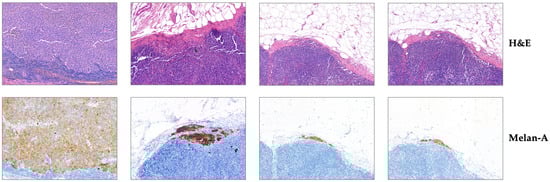

ClinSegNet: Towards Reliable and Enhanced Histopathology Screening

by Boyang Yu, Hannah Markham, Karwan Moutasim, Vipul Foria and Haiming Liu

In histopathological image segmentation, existing methods often show low sensitivity to small lesions and indistinct boundaries, leading to missed detections. Since, in clinical diagnosis, the consequences of missed detection are more serious than false alarms, this study proposes ClinSegNet, a recall-oriented and human-centred [...] Read more.

In histopathological image segmentation, existing methods often show low sensitivity to small lesions and indistinct boundaries, leading to missed detections. Since, in clinical diagnosis, the consequences of missed detection are more serious than false alarms, this study proposes ClinSegNet, a recall-oriented and human-centred framework for reliable histopathology screening. ClinSegNet employs a composite optimisation strategy, termed HistoLoss, which balances stability and boundary refinement while prioritising recall. An uncertainty-driven refinement mechanism is further introduced to target high-uncertainty cases with limited fine-tuning cost. In addition, a clinical data processing pipeline was developed, where pixel-level annotations were automatically derived from IHC-to-H&E mapping and combined with public datasets, enabling effective training under limited clinical data conditions. Experiments on the NuInsSeg and NuInsSeg-UHS datasets showed that ClinSegNet achieved recall scores of 0.8803 and 0.8917, further improved to 0.8983 and 0.9053 with HITL refinement, while maintaining competitive Dice and IoU. Comparative and ablation studies confirmed the complementary design of the framework and its advantage in capturing small or complex lesions. In conclusion, ClinSegNet provides a clinically oriented, recall-prioritised framework that enhances lesion coverage, reduces the risk of missed diagnosis, and offers both a methodological basis for future human-in-the-loop systems and a feasible pipeline for leveraging limited clinical data. Full article

Show Figures

Graphical abstract